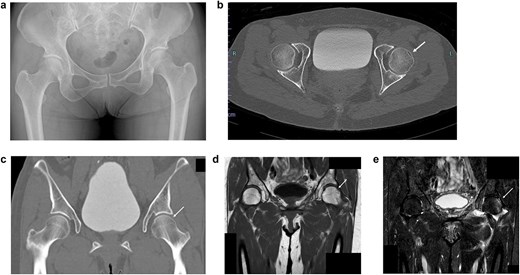

A 52-year-old woman was involved in a frontal motor vehicle collision while seated in the rear seat. At the time of impact, she was in a position of hip flexion, mild abduction, and external rotation (Fig. 1), a posture known to predispose to anterior dislocation. She presented to the emergency department with acute, severe left hip pain, and an inability to actively extend the affected limb. Plain radiographs and computed tomography (CT) scans revealed an obturator-type anterior hip dislocation without any accompanying fractures. Notably, a small depression was detected on the anterolateral articular surface of the femoral head (Fig. 2a–d). Based on the imaging and clinical findings, she was diagnosed with a traumatic obturator dislocation of the hip.

Imaging results at the time of transport. (a) Initial pelvic radiograph showing left femoral head dislocation. (b) Axial CT image showing femoral head displaced into the obturator foramen. (c) Coronal CT image showing inferior and medial displacement of the femoral head. (d) 3D reconstructed CT image showing the femoral head in the obturator foramen.